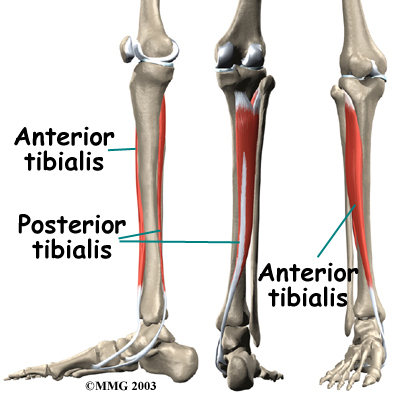

The lower leg is made up of . The shinbone is the larger of the two bones. It is called the tibia. The small, thin bone that runs alongside the tibia from the knee to the ankle is the fibula.

The tibia and fibula provide a connecting point for several muscles that move the foot. The main muscle that bends the foot upward connects on the front (anterior) of the tibia. It is called the anterior tibialis. The posterior tibialis, which pulls the foot down and in, attaches along the back (posterior) and inside edge of the tibia. Together, the anterior and posterior tibialis muscles are called the tibialis muscles.

The tibialis muscles have that fasten the muscle to the bony surface of the tibia. This bony covering, or membrane, is called the periosteum (peri means around, and osteum means bone).

Shin splints usually result from overuse. Repeated movements of the foot can cause damage where the tibialis muscles attach to the tibia. Soon the edge of the muscles may begin to pull away from the bone. The injured muscle and the bone covering (the periosteum) become inflamed.

Anterior shin splints tend to affect people who take up a new activity, such as jogging, sprinting, or playing sports that require quick starts and stops. The unfamiliar forces place a heavy strain on the anterior tibialis muscle, causing it to become irritated and inflamed. This commonly happens when people who aren't regular runners decide to go on a long jog. The anterior tibialis muscle must work hard to control the landing of the forefoot with each stride. Running downhill puts even more demands on this muscle in order to keep the forefoot from slapping down. People who run on the balls of their feet or who run in shoes with poor shock absorption also tend to get anterior shin splints.

Posterior shin splints are generally caused by imbalances in the leg and foot. Muscle imbalances from tight calf muscles can cause this condition. Imbalances in foot alignment, such as having (called pronation), can also cause posterior shin splints. As the foot flattens out with each step, the posterior tibialis muscle gets stretched, causing it to repeatedly tug on its attachment to the tibia. The posterior tibialis muscle attachment eventually becomes damaged, leading to pain and inflammation along the inside edge of the lower leg.